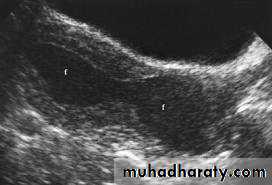

Transabdominal scanned image

• Rupture of hemorrhagic ovarian cyst:

Transvaginal scanned image